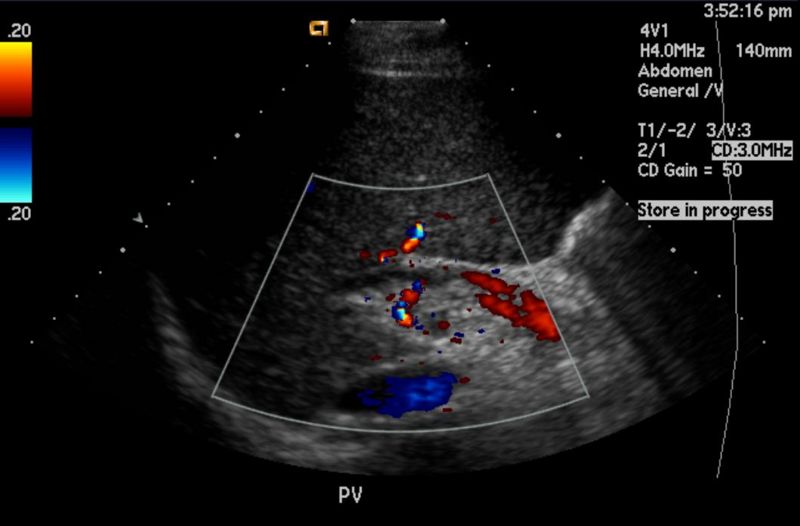

Enfermedades del sistema digestivo y abdominal

La tomografía abdominal es fundamental para diagnosticar múltiples afecciones del aparato digestivo, del sistema urinario y de los órganos sólidos abdominales. Entre las enfermedades más frecuentes que se detectan con este estudio destacan:

Tumores hepáticos, renales o pancreáticos: detecta lesiones focales, evalúa su vascularidad y extensión.